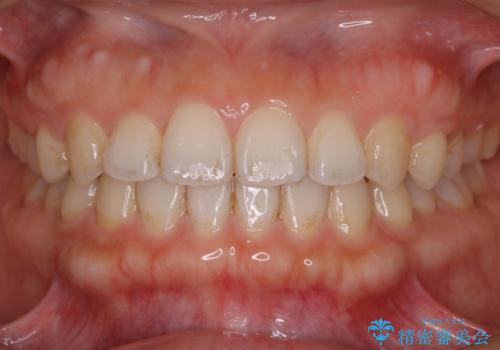

マウスピースで効率的にすきっ歯を治す

すきっ歯の場合、ガタつきを治したりするのに必要なスペースが最初から空いているため、そのスペースを利用して比較的短期間で効率よく治療を進めることが可能となります。

噛み合わせの治療

初診時の写真では一見噛み合わせには問題がないように見えても、実際に精密な検査を行うと改善すべき点が見つかる場合も多くあります。

当院では、矯正治療は見た目の改善が主目的ではなく機能面を改善し自然に長持ちする口腔内環境を整えることに重きを置く必要があると考えます。

しかしながら、こちらの理想だけを押し付けるだけが良い治療とは言えないので、患者様と治療のゴールの設定をよく話し合ったうえで方針を決定していくことが最も重要です。